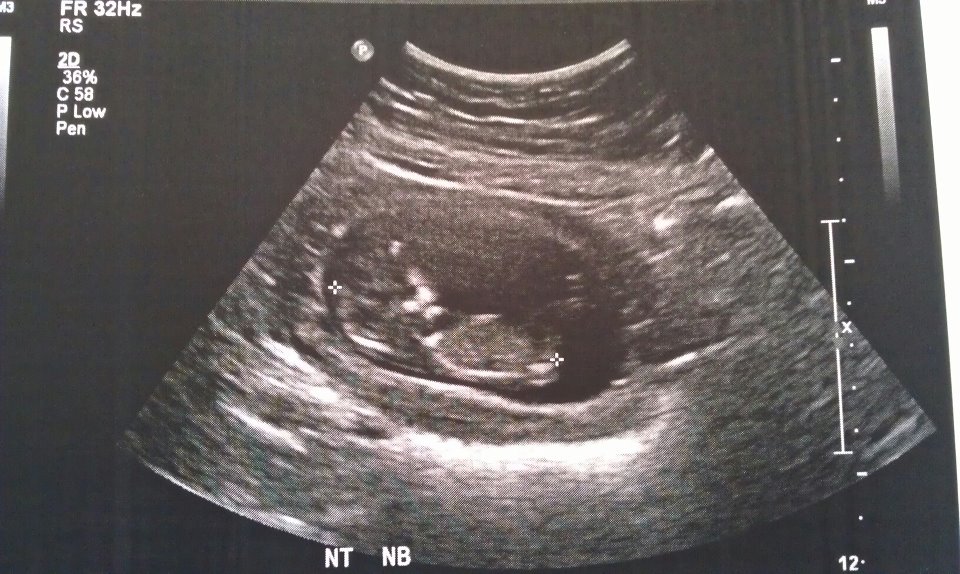

HI everyone just wondering what is everyone thoughts about our new bubba, we have a 2 year old daughter. Thanks

TOTAL...BOY!

Nub...is...tilted/pointed...upwards!!!

Thanks for such a quick reply ! I did, mostly boy guesses, but a tech said girl so now im confused, and wanted to try this site aswell. I think the tech said girl because of the second photo because of the fork in the nub and also because the end of the spine isnt visble. I think that it could go either way because the nub isnt 30 degrees but then its not pointing down either. My DD's nub was pointing really far down so it was obvious, but this one is driving me mad lol 5 more days till we find out!!! WOO HOO!

cracker, this is what I was thinking? Also baby is quite curled and I'm seeing the nub quite in line with it if i straighten baby out. But! The nub does look quite fat so thinking boy and it doesn't seem to be completely attached to the body so leaning boy on that one also. I would have to say 65/35 boy on your nub but will be waiting anxiously on your result, hope you hear blue: What is the gestation??